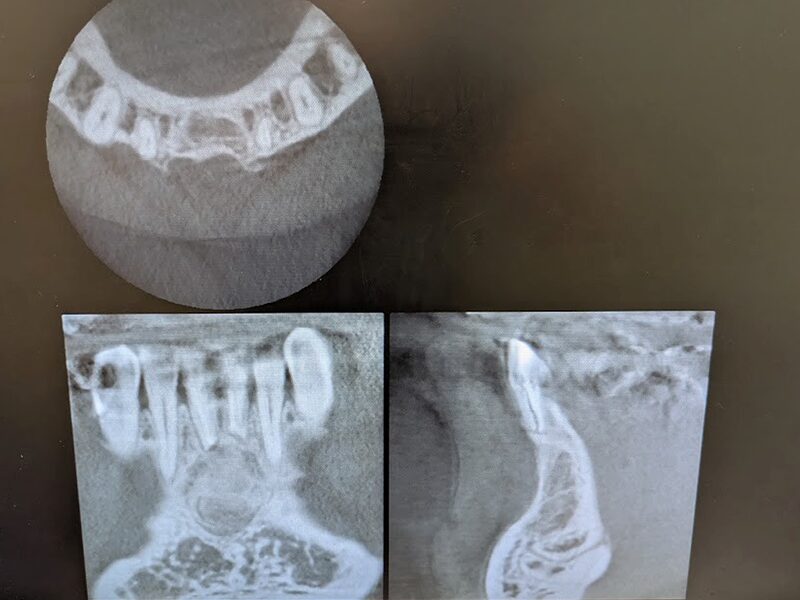

下顎前歯1番(中切歯)の歯根の先端部に透過像を認めます。

初診時のCT画像所見です。下顎前歯部の骨が大きく吸収していることが分かります。

術後1年経過しています。CT画像から骨の再生が起きていることが確認されました。特に頬側の皮質骨が再生しています。